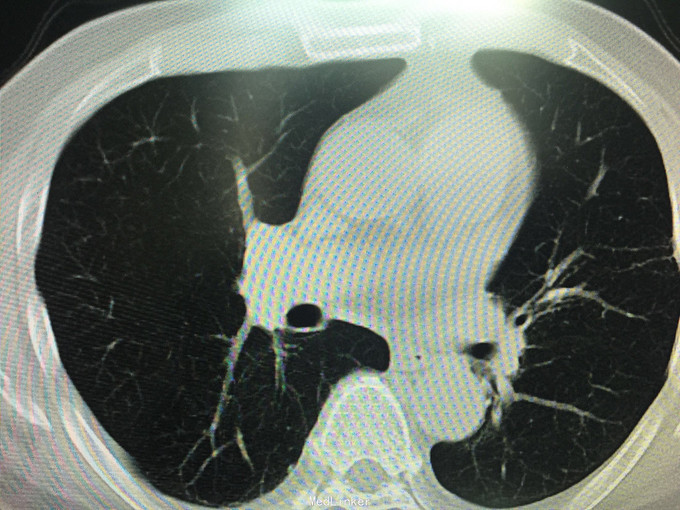

男性,70岁, 主诉:发现左肺上叶占位12个月 现病史:2014.10月患者出现胸背部疼痛不适,对症理疗未见好转。2014.11月出现咳嗽,咳痰带血丝,行胸部CT检查示:左肺上叶占位病变,恶性可能性大。2014.11.13患者行PET/CT检查提示:左肺上叶软组织密度肿块影伴周围片状密度增高影,代谢增高,考虑恶性病变伴周围炎性改变。纵隔内及左肺门多发淋巴结影,代谢增高,考虑为恶性病变转移。左肾上腺结节,代谢增高,考虑为恶性病变转移。第2胸椎棘突骨质破坏,代谢增高,考虑为恶性病变转移。肿瘤标志物:CA125 625 U/ml。因肿块位置较高,未行纤维支气管镜取病理,患者因年龄大,拒绝行肺肿物穿刺活检,故病理不明确。但根据肿瘤影像学形态及理化检测,怀疑为腺癌,建议患者行TKI靶向治疗,同时给予双磷酸盐治疗骨转移。患者口服TKI一个月后复查胸部CT肿块明显缩小,胸背部疼痛消失。患者现口服TKI约11个月,无明显咳嗽咳痰,无背部疼痛。近1周,患者诉偶尔咯鲜红色粘痰,伴有咽部及胸前区闷痛疼痛无明显咳嗽症状,为求复查而来诊。复查胸部CT较之前对比未见明显变化。复查肿瘤标志物:CEA、CA-125、NSE均未见异常。

查体:BP 165/75mmHg,双肺呼吸引清,未闻及干湿罗音,心音钝,心律齐,心率72次/分,各听诊区未闻及杂音。腹平,未见胃肠型及蠕动波,腹软,全腹无压痛,无反跳痛及肌紧张,肝脾肋下未触及,墨菲氏征(-),移动性肝肾区无叩痛,移动性浊音(-),肠鸣音4次/分。 辅助检查:肝胆脾彩超:未见明显异常。 胸部CT:较2015.8月对比未见异常,左肺上叶陈旧性改变。 肿瘤系列:CEA、CA-125、NSE均未见异常。